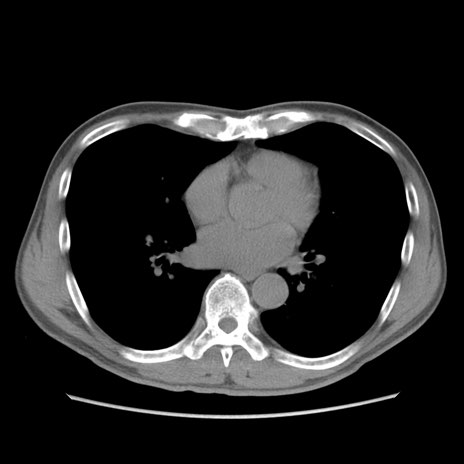

症例56 CT(横断像)

脂肪ウインドウ